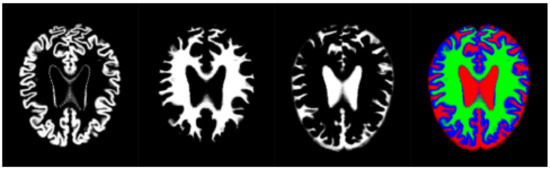

Thus, we have used an aggregation of the probability volumes for GM, WM and CSF to carry out a segmentation using supervoxels. In this respect, for segmentation purposes, the different probability volumes (which are represented as 8-bit intensity maps) can be equated to the spectral bands of a colour volume (see Figure 3). Using a supervoxel segmentation (over-segmentation), we get a way of characterizing the local similarities within the aggregate volume, obtaining a natural set of neighbourhoods for the generation of histons. Similarly to what can be seen in [53], the use of supervoxels as a neighbourhood implies the adherence of the neighbourhoods set to the boundaries and features present in the image, so, when a histon is calculated, there is a direct spatial relationship between the voxel tested for its belonging and the color sphere. Furthermore, we can quantify the overall local homogeneity of a volume using the average intensity standard deviation of the supervoxel-defined space since segmentation using supervoxels already produces locally homogeneous areas.

Figure 3. Volume slice from the pre-processed OASIS-1 dataset, showing tissue segmentation probabilities and its corresponding aggregate slice as an RGB image. Gray matter probabilities (left), white matter probabilities (middle left), cerebrospinal fluid (middle right) and aggregate (right) (Gray matter probabilities as blue, white matter probabilities as green, cerebrospinal fluid as red).